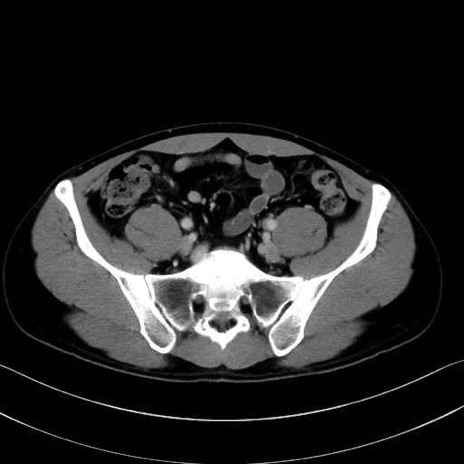

2. 腸腰筋群と骨盤底筋

大腰筋 (Psoas major)

腸骨筋 (Iliacus)

肛門挙筋 (Levator ani)